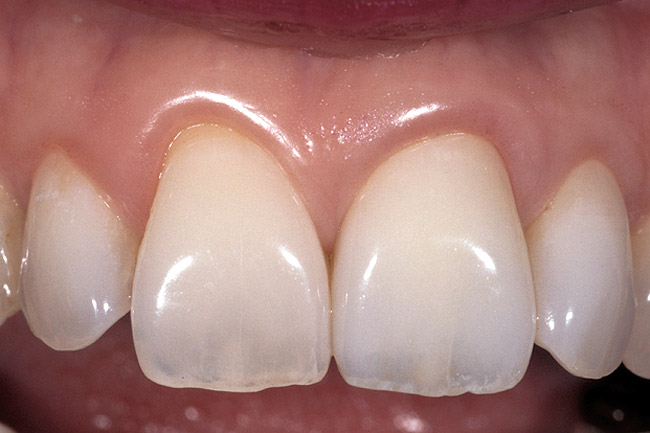

Figure 3  Dark teeth or teeth requiring restorations that are more opaque for masking often require the margin to be carried subgingivally, as with this central and lateral incisor.

Figure 3

Figure 4  View of the completed central and lateral incisor with margins placed subgingivally, but maintaining tissue health.

Figure 4

The most common reasons to extend a margin below tissue are: caries below gingiva; old restorations that already exist below gingiva; to achieve adequate tooth preparation length for proper retention and resistance; to make significant contour alterations; to hide the margin when the tooth is discolored (Figure 3 and Figure 4); and to hide the margin when the restorative material of choice demonstrates optical properties different from those of the natural tooth such that the margin would be highly visible. Regardless of why a subgingival margin is chosen, there are 2 negative responses that may occur.